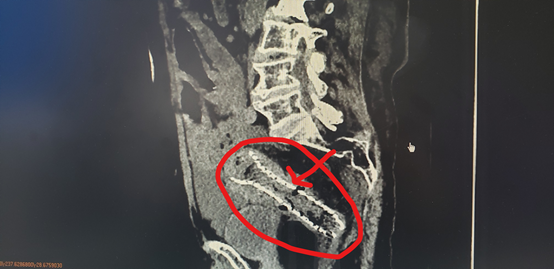

老年男性,腹胀无排便4+天,因为剧烈腹痛、腹胀入院。本院CT提示结肠梗阻,可见明显肠壁增厚,提示肠癌可能。

▲腹部CT片可见扩张明显的肠管

▲术后第三天复查CT

可见患者肠梗阻梗阻完全消失,支架完全打开